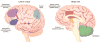

Functional and structural neuroimaging have identified abnormalities of the brain that are likely to contribute to the neuropathophysiology of attention-deficit/hyperactivity disorder (ADHD). In particular, hypofunction of the brain regions comprising the cingulo-frontal-parietal cognitive-attention network have been consistently observed across studies. These are major components of neural systems that are relevant to ADHD, including cognitive/attention networks, motor systems, and reward/feedback-based processing systems. Moreover, these areas interact with other brain circuits that have been implicated in ADHD, such as the "default mode" resting state network. The ADHD imaging data related to cingulo-frontal-parietal network dysfunction will be selectively highlighted here to help facilitate its integration with the other information presented in this special issue. Together, these reviews will help shed light on the neurobiology of ADHD.